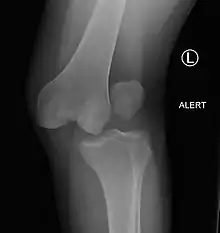

| Plain lateral X-ray of the left knee showing a posterior knee dislocation[1] | |

- ↑ Duprey K, Lin M (February 2010). "Posterior knee dislocation". The Western Journal of Emergency Medicine. 11 (1): 103–4. PMC 2850837. PMID 20411095.